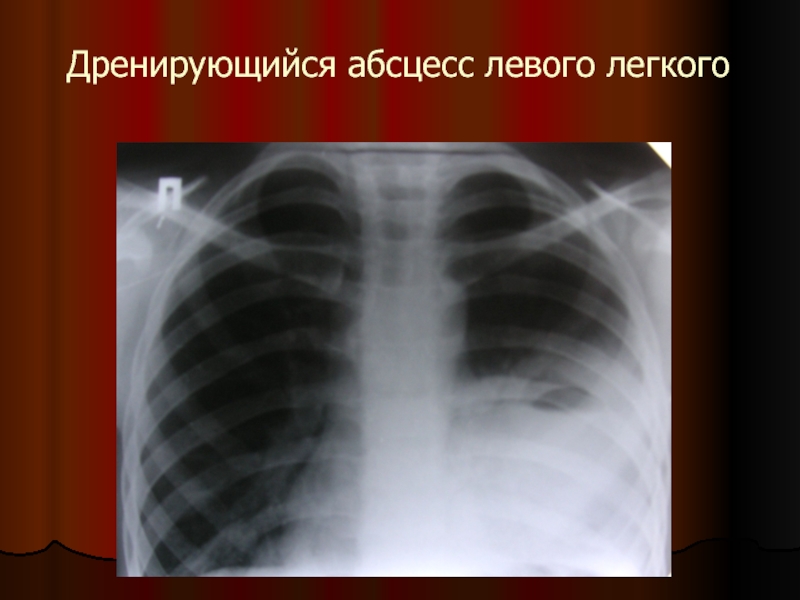

Слайд 27Дренирующийся абсцесс левого легкого